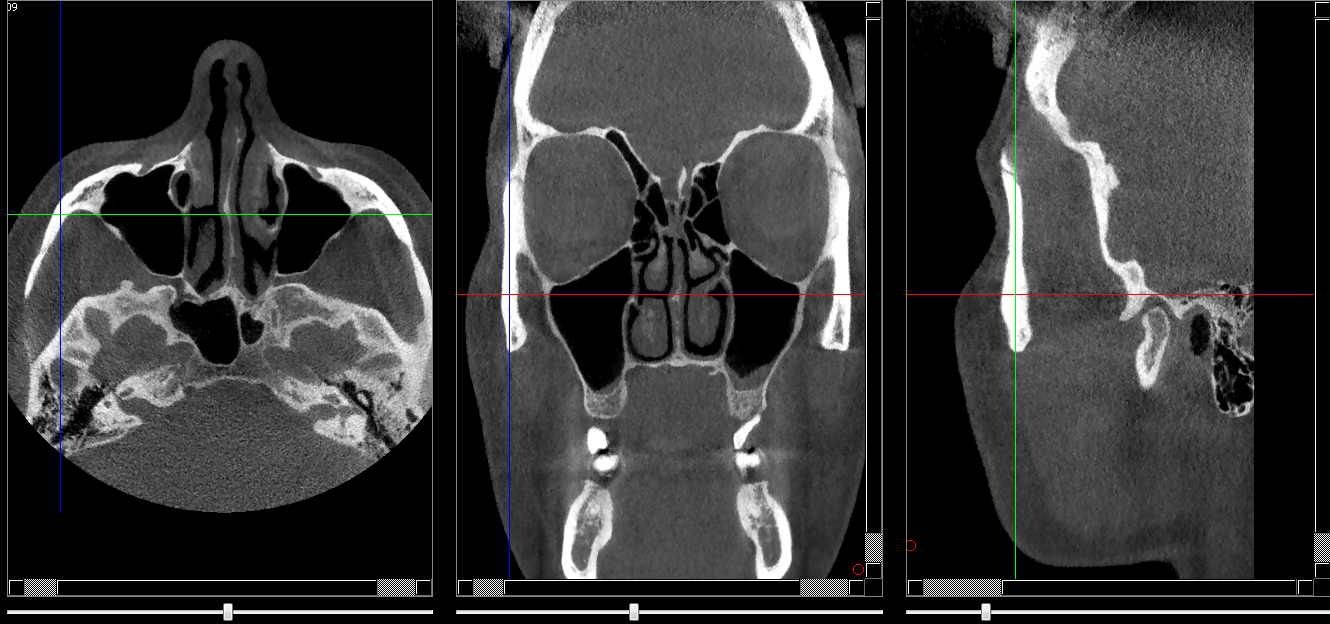

Structures osseuses

Zygoma

Repères anatomiques

- Coupe transversale

- Début : Milieu du sinus

- Fin : Suture fronto-zygomatique

- Coupe frontale

- Début : Plafond du sinus maxillaire

- Fin : clivus(paroi post du sinus sphénoidal)

- Coupe saggitale

- Début : Paroi externe du zygoma

- Fin : Partie externe du sinus maxillaire